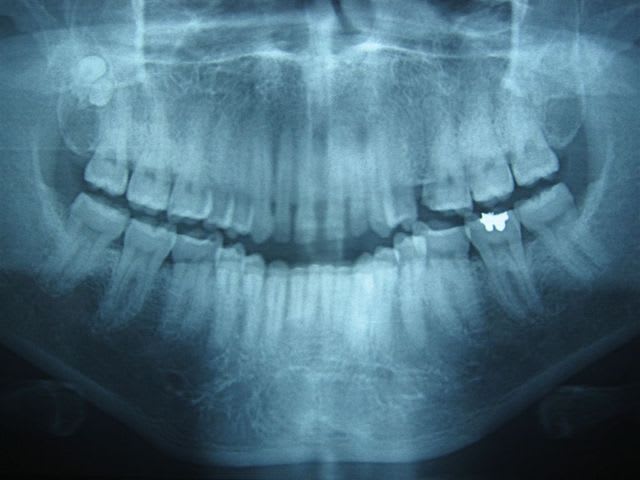

... si vous savez compter ...

... dépassements de pâte ou de cônes d'argent ... même combat!

... comptez

... comptez ... les cônes d'argent!

... patiente née en 1946, endos datant d'une quarantaine d'années ... et pas de foyer ... la nature est bonne :)

Par contre pour sortir ces m*rdes, c'est la galère, ça casse très facilement.